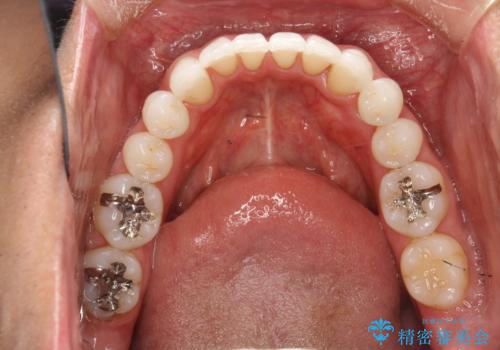

インビザライン終了時のPMTC

- インビザライン治療が終了し、アタッチメント除去の際にクリーニング(PMTC)も希望されました。

PMTC60分1万円+tax(保険適応外)を行いました。

インビザライン矯正治療は、歯にアタッチメント(歯を動かすための突起物)をつけます。そのため、矯正治療が終了し、アタッチメントを外すと着色が目立つことがあります。矯正治療の終了のタイミングではクリーニングを行い、着色の除去や歯と歯の間・歯と歯肉との境目などのケアをしっかりすることをおすすめしています。